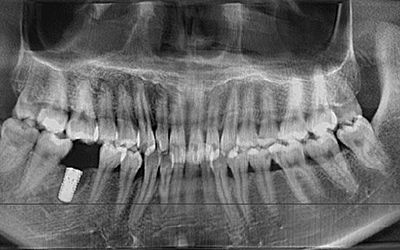

患者信息:刘女士 年龄:20岁

口腔症状:单颗牙缺失

检查结果:单颗牙缺失,牙齿排列整齐完好,无龋齿等症状,全口牙CT显示根尖无异常。

牙齿补救方案:通过口腔数码内窥镜及口腔全景机,精确定位缺牙部位,运用先进的微数字化种植牙技术进行种植。